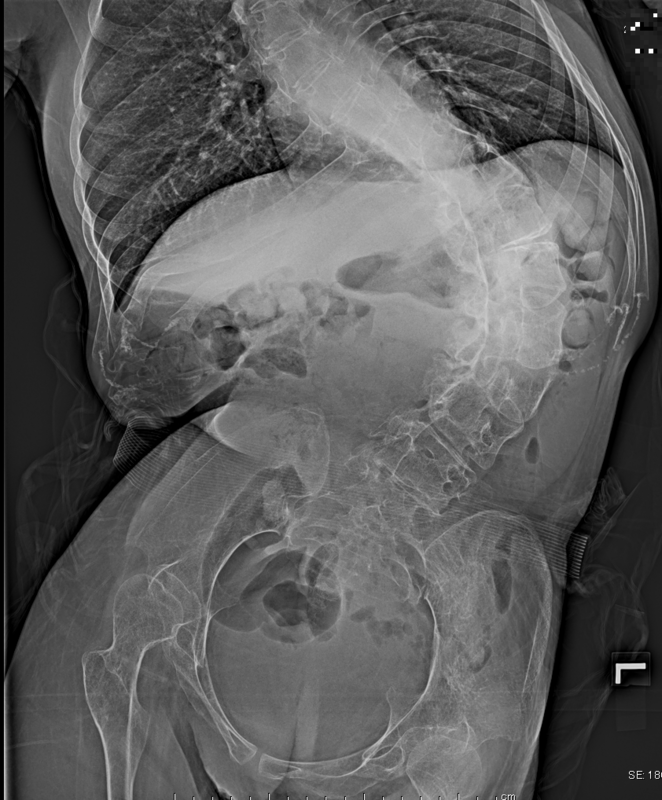

Ⅲ型(クーゲルベルグ・ウェランダー病)の場合、発症年齢が1歳6か月~20歳までと幅広いため、患者さんごとに経過はさまざまです。ただ、Ⅲ型の患者さんは立って歩けていたという経験を持っているため、次第に転びやすくなる、しゃがんだ状態から脚の力だけで立てなくなる、階段が上りづらくなるといった症状で発症に気づきます。歩行時には、体幹、臀部の筋力低下の影響で、腰を左右に揺らして歩くようになります。さらに進行すると歩けなくなり、さらに上肢にも症状が及び、腕を挙げられなくなるといった症状が出現します。そのほかの特徴として挙げられるのが、背骨が左右に弓のように曲がる側彎で、これは特に発症年齢が若いほど見られやすい症状です。